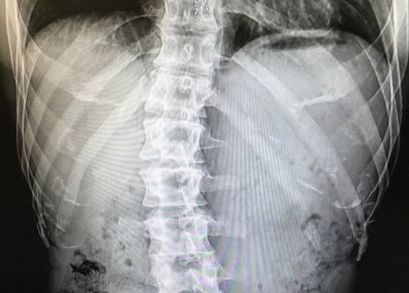

但你知道吗?他的椎间盘从中学开始就不好

直到现在……已经这么严重了

虽说健身有效的缓解了的金钟国的腰伤

但是98年至今20多年的时间内

腰伤依旧会时不时的复发

并且膏药对如今的他已经没有了任何作用